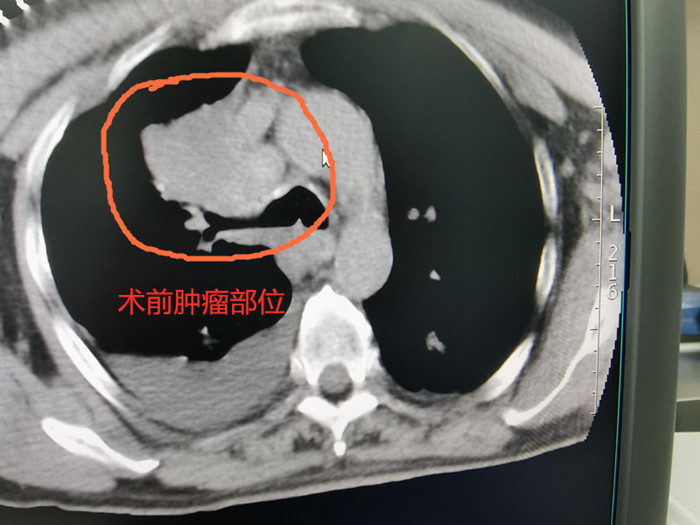

68歲的吳老伯因確診右上肺鱗癌收治入院,腫瘤侵犯胸膜及上腔靜脈,失去手術(shù)根治切除的機會,放化療效果也不理想。經(jīng)過多次討論,腫瘤放療團隊決定為他實施共面模板引導下放射性粒子植入術(shù)。

術(shù)前CT